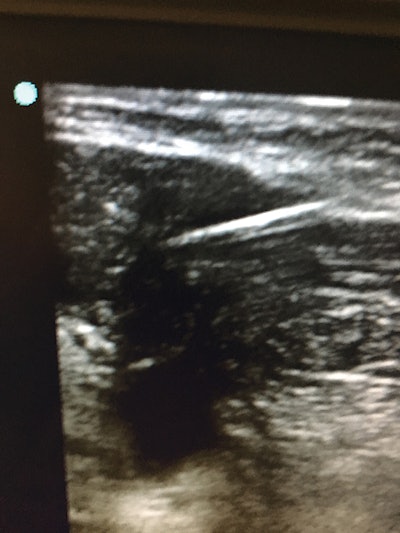

Figure 2: Photo of an ultrasound needle aspiration of a plunging ranula.Office-based ultrasonography is becoming an increasingly important tool within head and neck surgery practices. Ultrasonography allows real-time, on-site imaging of a variety of lesions in the thyroid, salivary glands, and lateral neck. Advantages of the technique include efficiency, ability to perform image-guided fine-needle aspiration (FNA) (Figure 2), ability to follow lesions over time without concern for excess radiation exposure, lack of need for contrast enhancement, and relative low cost. It provides additional revenue potential for offices that integrate the findings of U.S. examination within their electronic medical records (EMRs). More recently, several academic head and neck practices have combined office-based ultrasonography with radiofrequency ablation of symptomatic, compressive thyroid nodules not suspicious for cancer following adequate fine-needle aspiration. By applying a radiofrequency probe via percutaneous technique under ultrasound guidance, surgeons are able to achieve up to 50%-80% volume reduction without surgery in select symptomatic nodules. The slower adoption of office-based ultrasonography in the U.S. compared to Europe is likely due to lack of exposure to the technique during residency training, therefore appropriate coursework and ongoing medical education are required for its successful application.